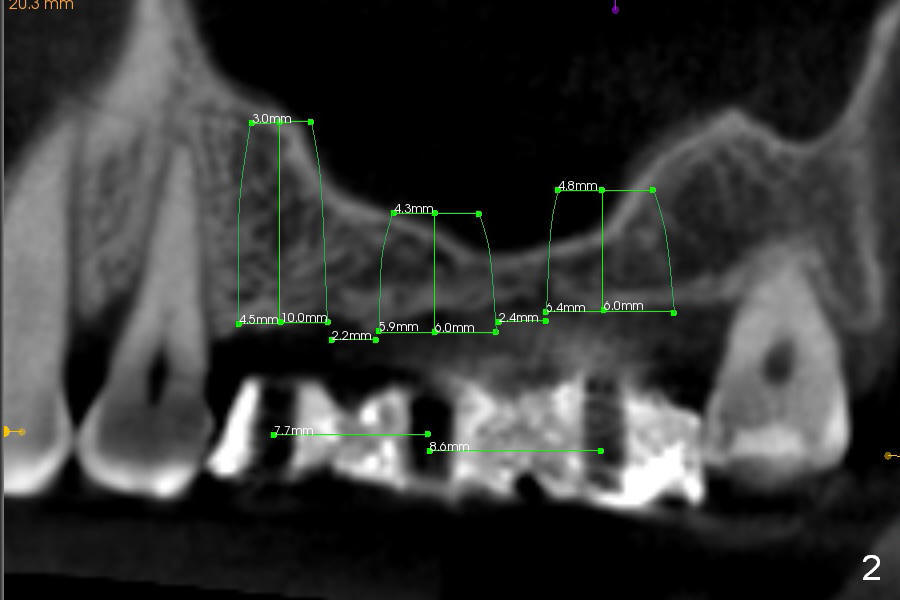

A 49-year-old lady has lost #2-4 for quite a while (Fig.1, no indication for antibiotic study (for cases with <6 months post extraction)). Bone height at #2 and 3 is limited. Use a 2 mm pilot drill to start osteotomy with rubber stopper at 4 mm, followed by insertion of 2 short parallel pins (PP) at #2 and 3 (Fig.2,4,6,8). The PPs may be not stable because of shortness. At #4 (8 mm initially), insert a marked PP for PA. If the position and trajectory of each osteotomy is correct, use trephine burs for further osteotomy at #2,3, since they have labels of 2,4,6 mm. For example small one at 4 mm, larger one at 6 mm. If the bone stays in place after trephine bur usage, use Bicon osteotomes to do sinus lift. Allograft and Osteogen is to be loaded in small syringes (x4). Previous implant surgeries indicate that the bone density of the maxilla is high (1,2). CT shows variable density (compare Fig.1 vs. 2, 3 vs. 4 et al). The density at the medulla is low; that at the cortices high. The patient plans to have 2 implants. If the implant at #3 is not stable, the implant at #2 will be needed for splinting.